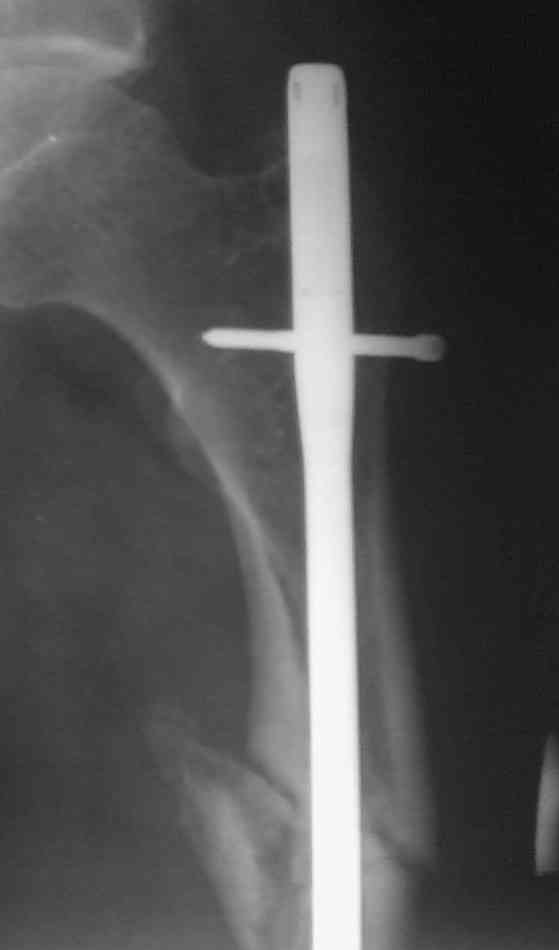

Однозначно: удалить, рассверлить, перештифтовать более толстым гвоздем. ЭТОТ 9 мм будет? Возьмите 12-14.

Дистально обязательно два винта! Проксимально можно один динамический. Больной будет счастлив на следующий же день!

Учитывая точку введения - верхушка б\вертела - что бы исправить варус взял бы соответствующий гвоздь: длинную Гамму или PFN или Recon

Судя по уровню перелома, винты в шейку избыточны, подойдет и диафизарный гвоздь. Все, что нужно, это тиски и труба. Загнуть сразу ниже отверстий градусов на 8-10, и вся недолга. Последние годы у нас это рутинная практика. Предызогнутые еще с завода гвозди неудобны тем, что они уже правый-левый.

Согласен, что закрытый реостеосинтез с рассверливанием и коррекцией оси - это то, что надо. Мы бы ввели в центральный отломок статических 2-3 винта, и один динамический винт в дистальном отломке.